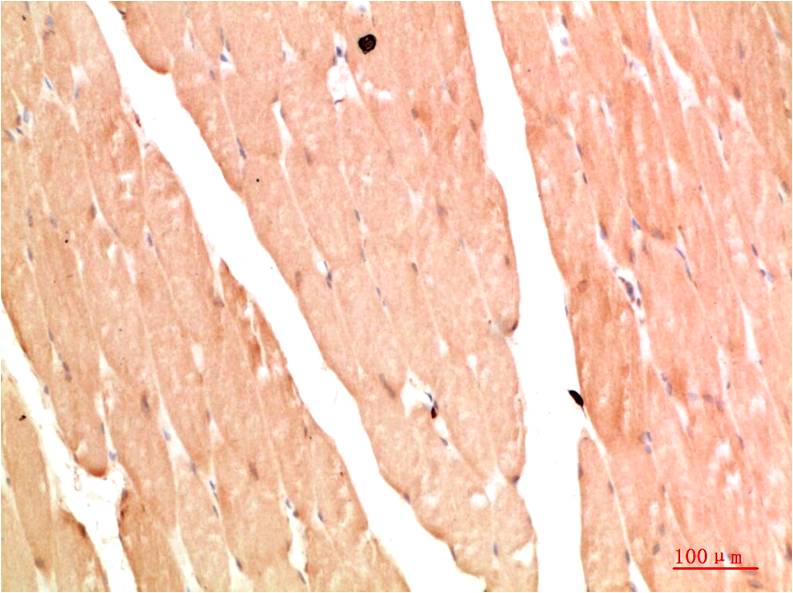

Acetyl P53(K382) Mouse Monoclonal Antibody(5H10)

Applications :IHC

| Recommended dilutions: | IHC: 1:100-200 |

| Specificity: | The Acetyl P53(K382) Mouse Monoclonal Antibody can detects endogenous Acetyl P53(K382) proteins. |